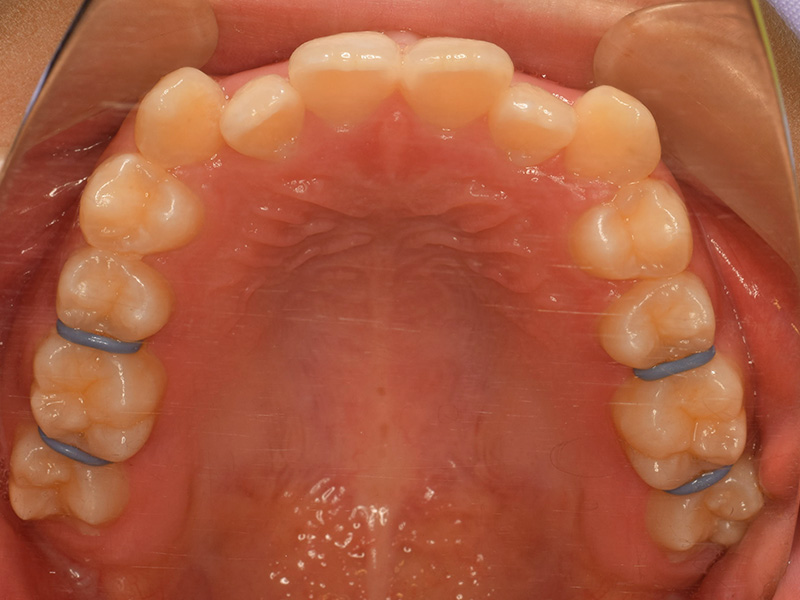

1、セパレーション

奥歯に隙間を作るために歯と歯の間にゴムを入れます。